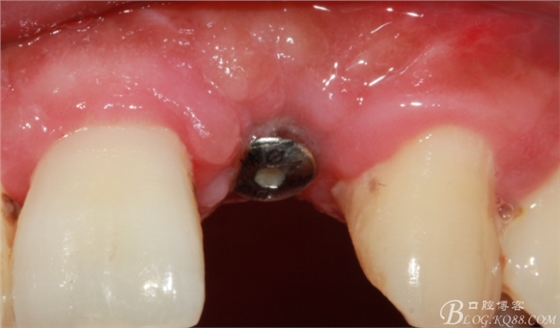

10天拆線一切正常,又過了兩周患者復(fù)診,自述期間無異常。口內(nèi)檢查,真的嚇了一跳,唇側(cè)鼓了個(gè)包,擠壓有白色分泌物溢出,絕對(duì)不是膿液,液體排除后,術(shù)區(qū)觸診空虛,外觀塌陷。這時(shí)候考研大夫的時(shí)刻到了,是先觀察一段時(shí)間再說?還是馬上進(jìn)行處理?我的回答是:馬上處理!如果你沒有及時(shí)處理,而是放患者回家觀察,那么接下來會(huì)發(fā)生如下情況:1.回家后患者家屬及親友會(huì)有很多你可以想象得到的討論;2.患者及家屬會(huì)對(duì)你產(chǎn)生不信任,勢(shì)必會(huì)到其他門診或醫(yī)院檢查,他院大夫會(huì)不會(huì)發(fā)表對(duì)你不利的言論;3甚至?xí)蚁嚓P(guān)法律界人士找你討要說法。

于是我果斷告知患者,手術(shù)失敗了,不能拖延,如不及時(shí)處理,炎癥繼續(xù)發(fā)展會(huì)很快波及鄰牙牙槽骨。患者接受我的建議。切開翻瓣,骨粉及生物膜消失了,骨吸收嚴(yán)重,幸運(yùn)的是,因?yàn)樘幚砑皶r(shí),鄰牙骨支持依然存在。